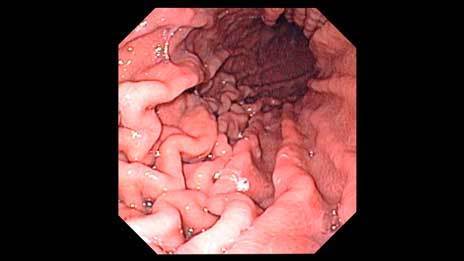

Describe the use of endoscopes. Used to look inside the body - commonly the reproductive and digestive systems, and the urinary and respiratory tracts.

Explain the use of endoscopes. One bundle of fibre optics carries light using total internal reflection to the object and another returns an image for the doctor to view.